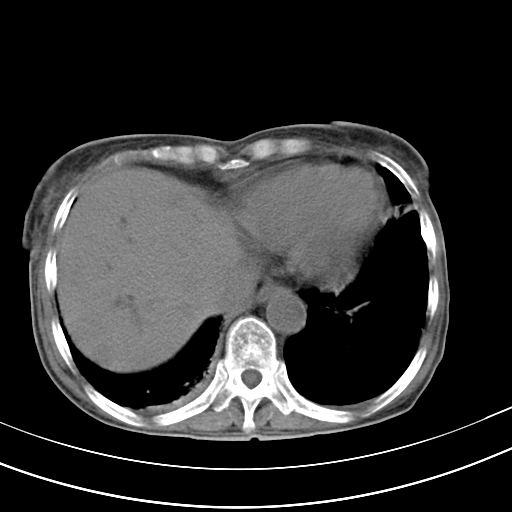

病人上腹部胀痛拌全身黄染八天

右侧少量胸水,胆囊增大,肝内胆管扩张,肝门部结构杂乱,建议增强。

肝内胆管及胰管扩张考虑为胰头区占位,肝门淋巴结增多,肝内多发低密度影,考虑为转移。门脉高压,脾大,胆囊大。

肝内胆管及胰管扩张,胰头增大考虑为胰头区占位,肝门淋巴结增多,考虑为转移。建议增强,脾大,胆囊大,壁厚,慢性胆囊炎。胃壁好像也增厚,且有一肿物。

1)考虑胰头癌并胆系低位梗阻;建议行ct增强扫描检查。2)慢性胆囊炎。3)脾大。4)少量腹水。5)双侧少量胸腔积液。